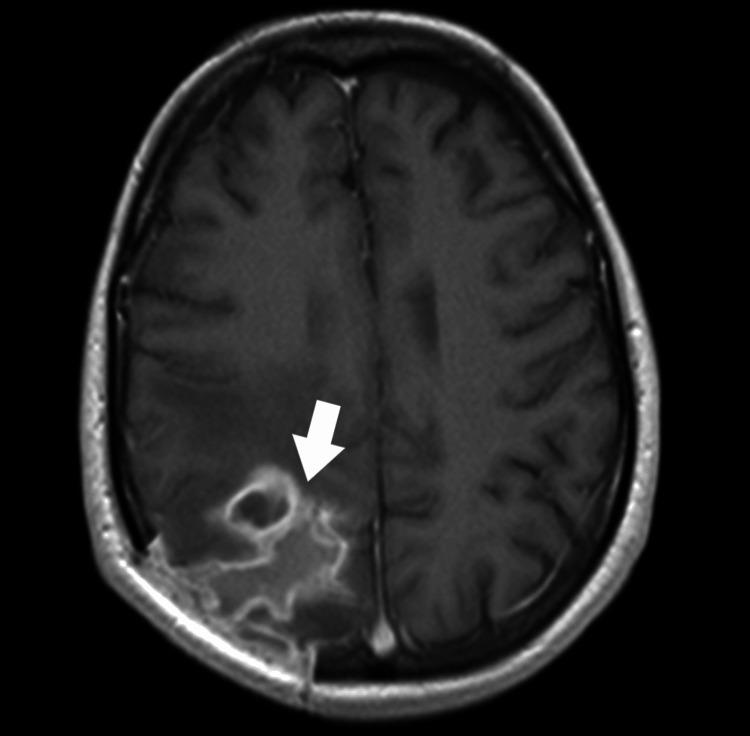

A brain abscess (BA) is a purulent infection of the central nervous system and can be associated with dental procedures. The paper presents a case of a patient diagnosed with an odontogenic BA. On admission, the patient was awake, alert, and oriented (Glasgow Coma Scale 15). The patient reported undergoing excision and drainage of an abscess in the submandibular area three years earlier. An MRI of the head showed a mass lesion (34x19x25 mm) located in the right parieto-occipital region, and an abscess was suspected. During the procedure, puncture and evacuation of the contents of the abscess in the right parieto-occipital area were performed. Oral microorganisms, including and , were isolated from the brain pus. A thorough radiographic and dental examination should be conducted during hospitalization in these patients. Always evaluate for periapical pathology in unexplained BAs, even in the absence of oral symptoms.

脑脓肿(BA)是中枢神经系统的化脓性感染,可能与牙科手术有关。本文介绍了一例被诊断为牙源性脑脓肿的患者。入院时,患者清醒、警觉且定向力正常(格拉斯哥昏迷量表评分为15分)。患者报告三年前曾接受下颌下区脓肿的切除和引流手术。头部MRI显示右顶枕区有一个肿块病变(34×19×25mm),怀疑为脓肿。手术过程中,对右顶枕区脓肿内容物进行了穿刺和引流。从脑脓液中分离出包括[具体微生物名称1]和[具体微生物名称2]在内的口腔微生物。对这些患者住院期间应进行全面的影像学和牙科检查。即使没有口腔症状,对于不明原因的脑脓肿也应始终评估根尖周病变情况。